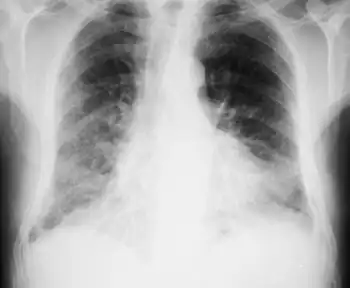

| Chest X-ray of combined pulmonary fibrosis and emphysema demonstrating bilateral interstitial pattern, predominantly right sided | |

CFPE is characterised by shortness of breath, and reduced oxygen concentration (reflecting gas exchange abnormalities). Imaging shows upper-lobe emphysema, and lower-lobe interstitial fibrosis.[4] CFPE is often complicated by pulmonary hypertension, acute lung injury, lung cancer, and coronary artery disease.[4]